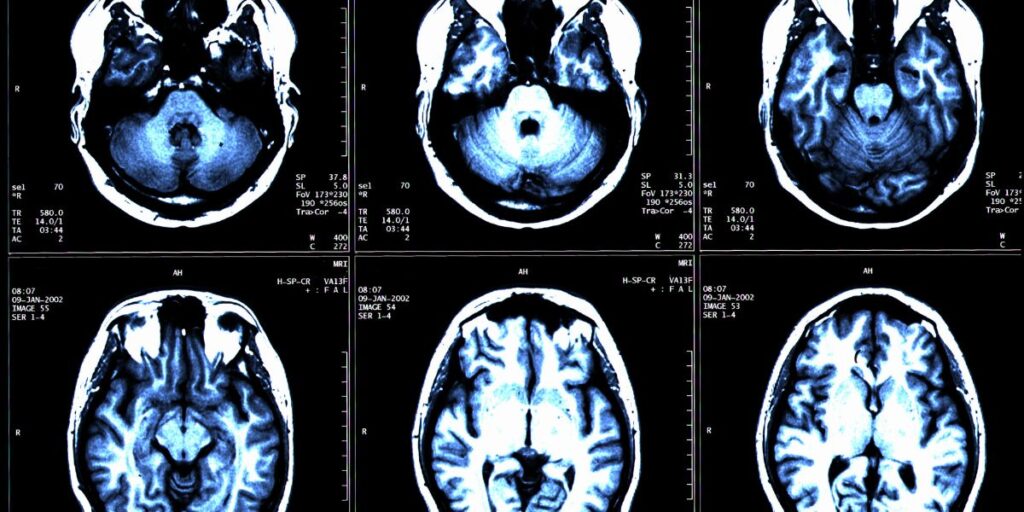

La Risonanza Magnetica Encefalo e Tronco Encefalico, nota anche come RMN encefalo e tronco encefalico, è una tecnologia di imaging medico avanzata che consente di ottenere immagini altamente dettagliate del cervello e del tronco encefalico. Presso il Poliambulatorio S-Medical Group di Sora, questo esame viene effettuato utilizzando strumenti moderni e con il supporto di un team di esperti altamente qualificati.

La Risonanza Magnetica Encefalo e Tronco Encefalico fornisce immagini di alta definizione delle strutture cerebrali. L’esame consente di visualizzare i lobi cerebrali, i ventricoli e il tronco encefalico, insieme ad altre aree cruciali del cervello. Presso il Poliambulatorio S-Medical Group di Sora, i medici possono ottenere immagini chiare e dettagliate, utili per identificare anomalie come tumori o altre condizioni patologiche.